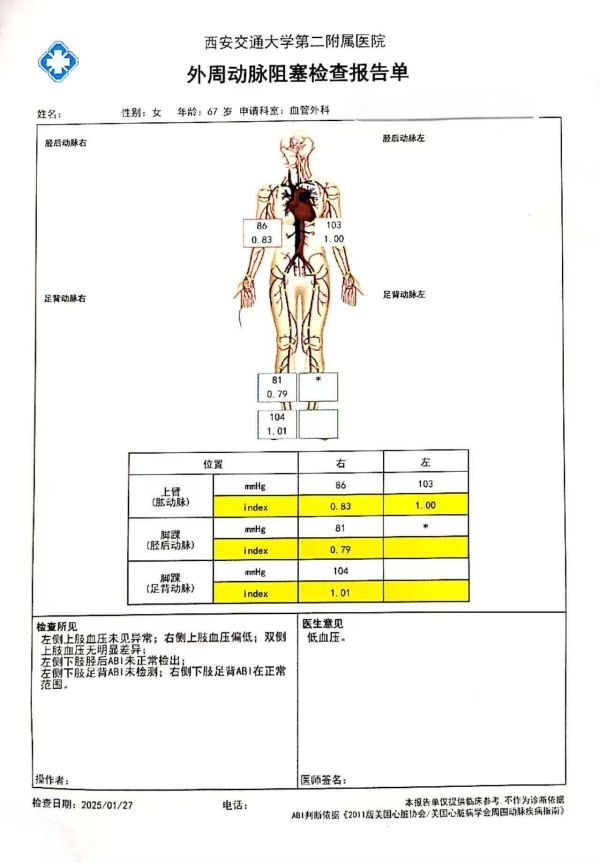

该患者入院ABI提示左下肢动脉搏动消失